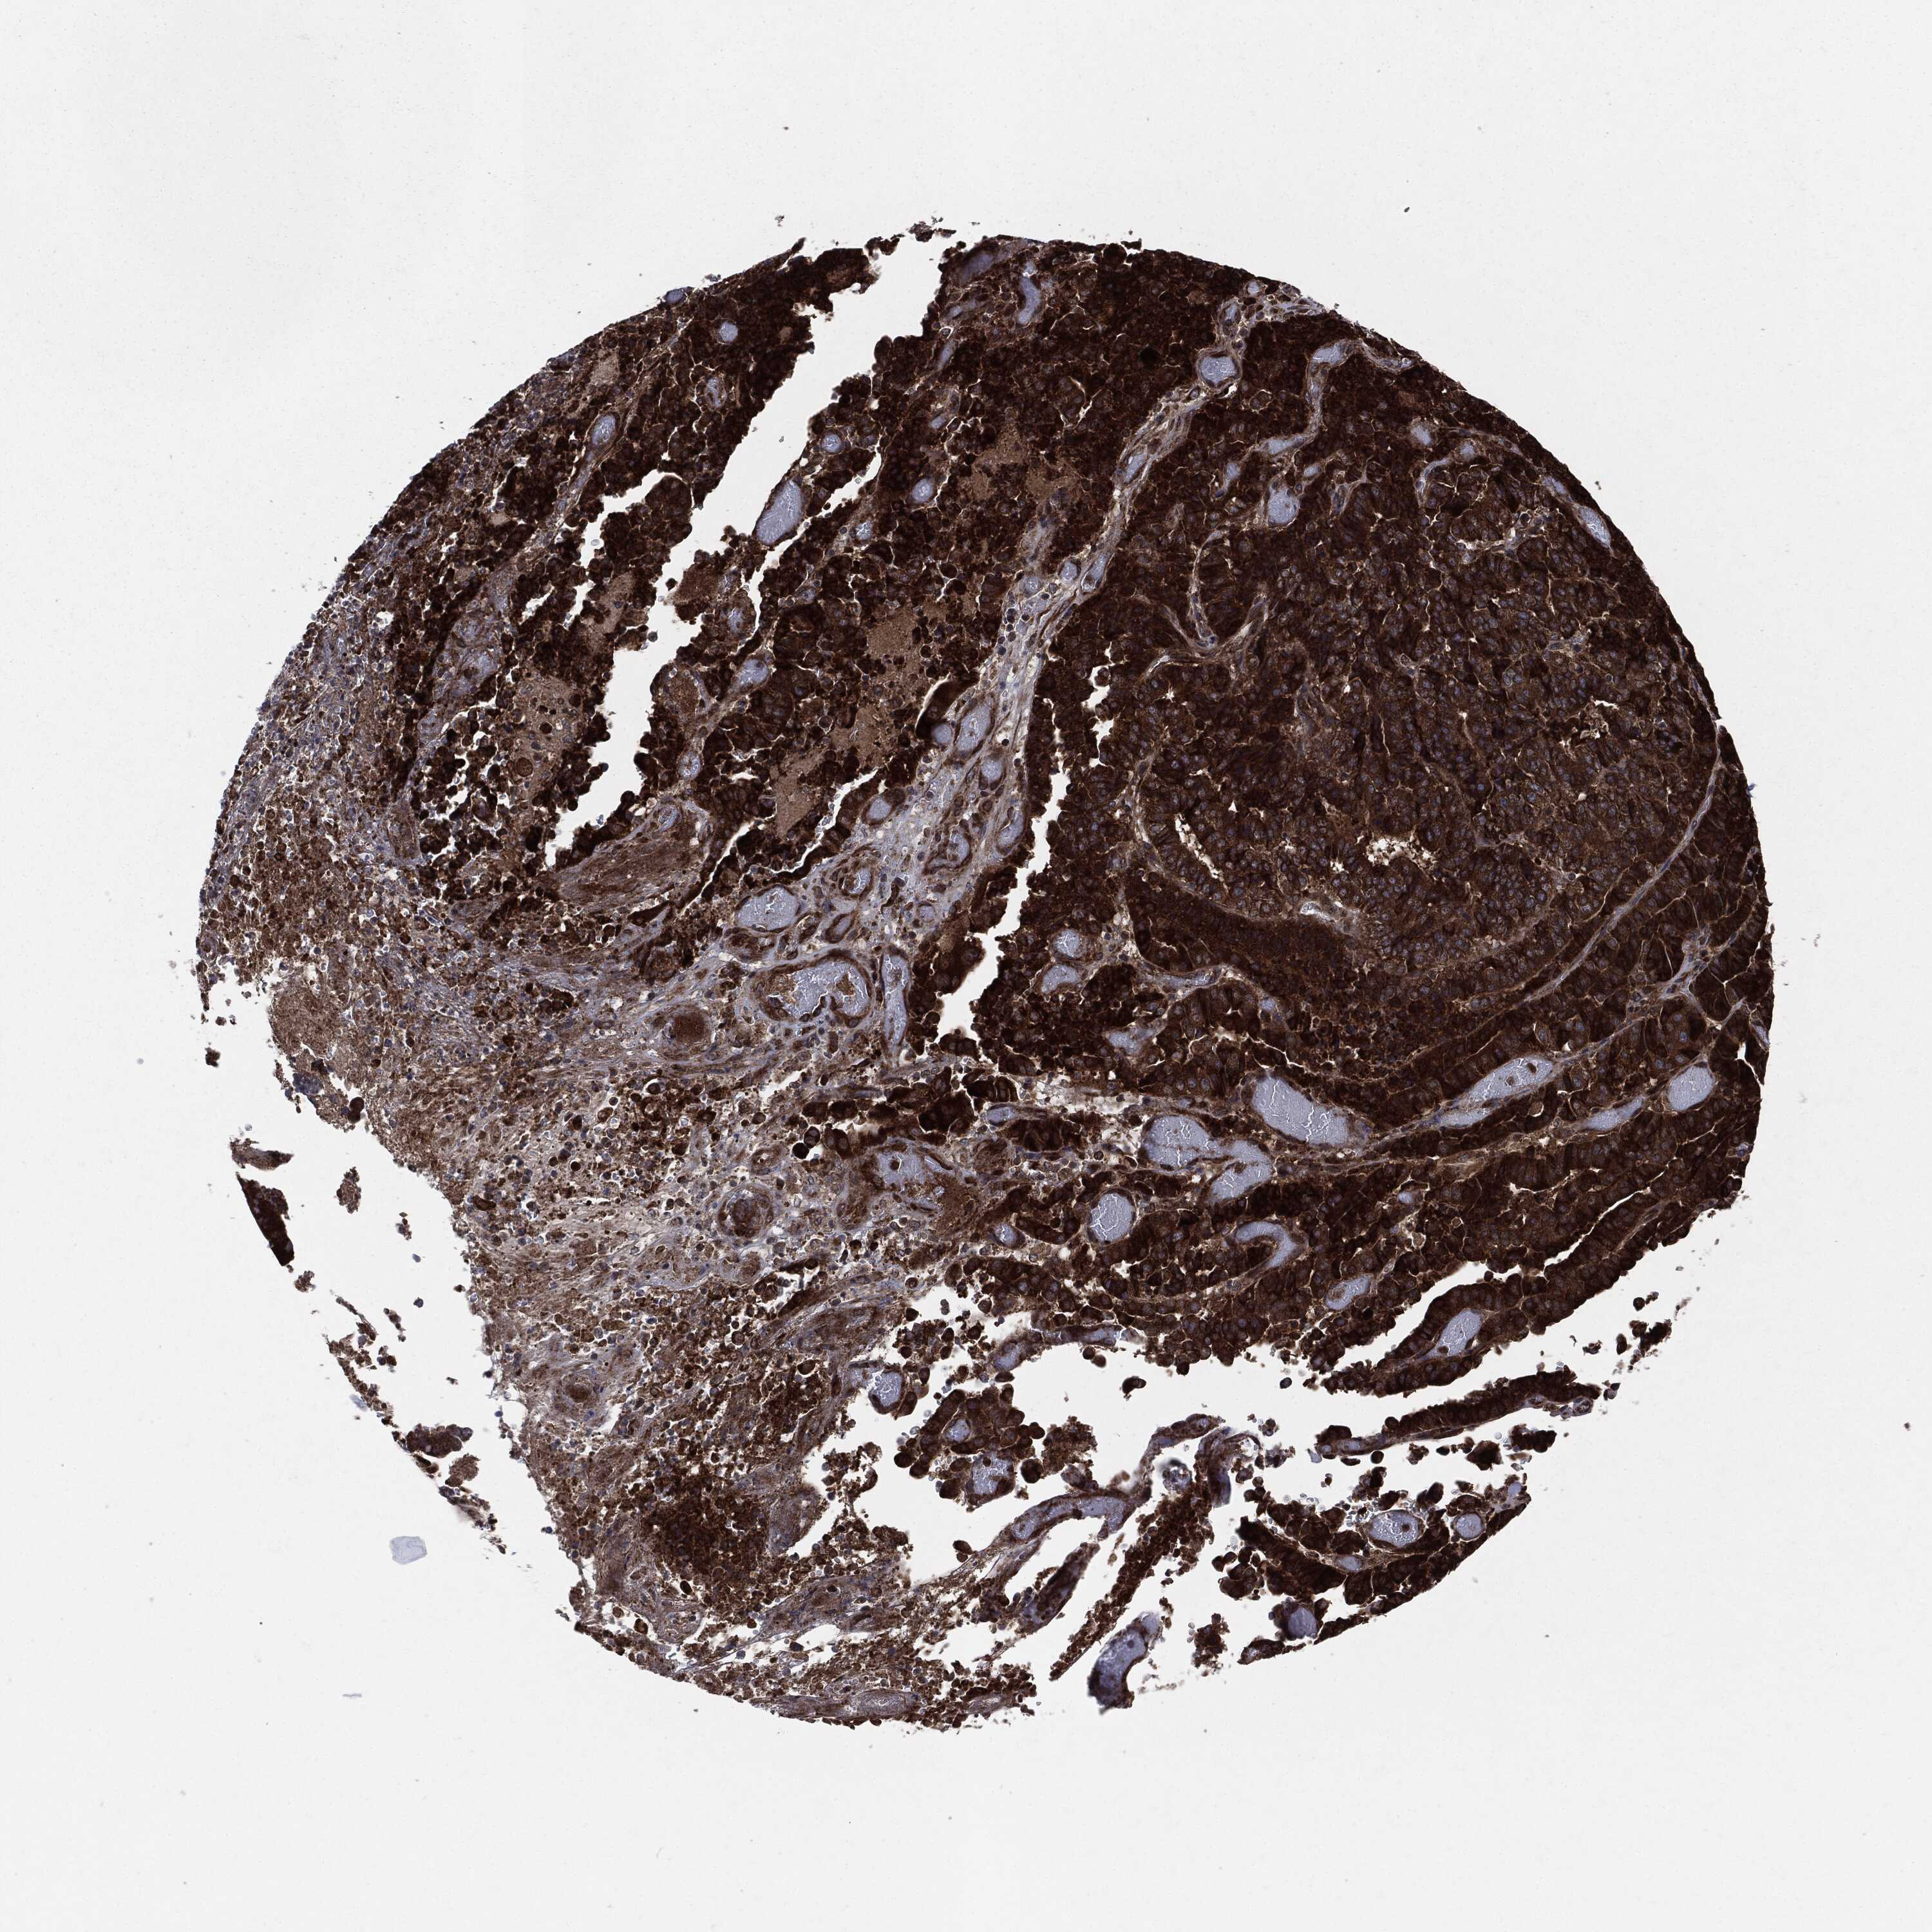

STOMACH CANCER - Protein expressioni

A mouse-over function shows sample information and annotation data. Click on an image to view it in a full screen mode. Samples can be filtered based on level of antibody staining by selecting one or several of the following categories: high, medium, low and not detected. The assay and annotation is described here.

Note that samples used for immunohistochemistry by the Human Protein Atlas do not correspond to samples in the TCGA dataset.

Antibody stainingi

Antibody staining in the annotated cell types in the current human tissue is reported as not detected, low, medium, or high, based on conventional immunohistochemistry profiling in selected tissues. This score is based on the combination of the staining intensity and fraction of stained cells.

Each image is clickable and will lead to virtual microscopy that enables deeper exploration of all samples and also displays staining intensity scores, fraction scores and subcellular localization as well as patient and tissue information for each sample.

Antibody HPA002640

Antibody CAB019291

Antibody CAB080384

Staining

High

Medium

Low

Not detected

Intensity

Strong

Moderate

Weak

Negative

Quantity

>75%

75%-25%

<25%

None

Location

Nuclear

Cytoplasmic/membranous

Cytoplasmic/membranous,nuclear

Adenocarcinoma, NOS

Adenocarcinoma, High grade